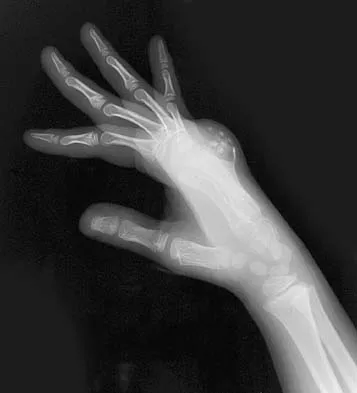

Question 71

A 9-year-old boy has a painless enlarged mass on the dorsum of his hand. Figures 14a through 14d show the clinical photograph, radiographs, and biopsy specimen. What is the most likely diagnosis?

Explanation

Multiple hereditary exostosis and enchondroma commonly present as multiple lesions in the hand. Multiple hereditary exostosis consists of cartilage capped bony exostoses arising from the metaphyseal end of rapidly growing bones. Osteosarcoma and chondrosarcoma rarely appear as multiple lesions. Fracture callus can exhibit enchondral ossification that is usually circumferential, but the radiographic findings are not consistent with fracture. Porter DE, Emerton ME, Villanueva-Lopez F, Simpson AH: Clinical and radiographic analysis of osteochondromas and growth disturbance in hereditary multiple exostoses. J Pediatr Orthop 2000;20:246-250.